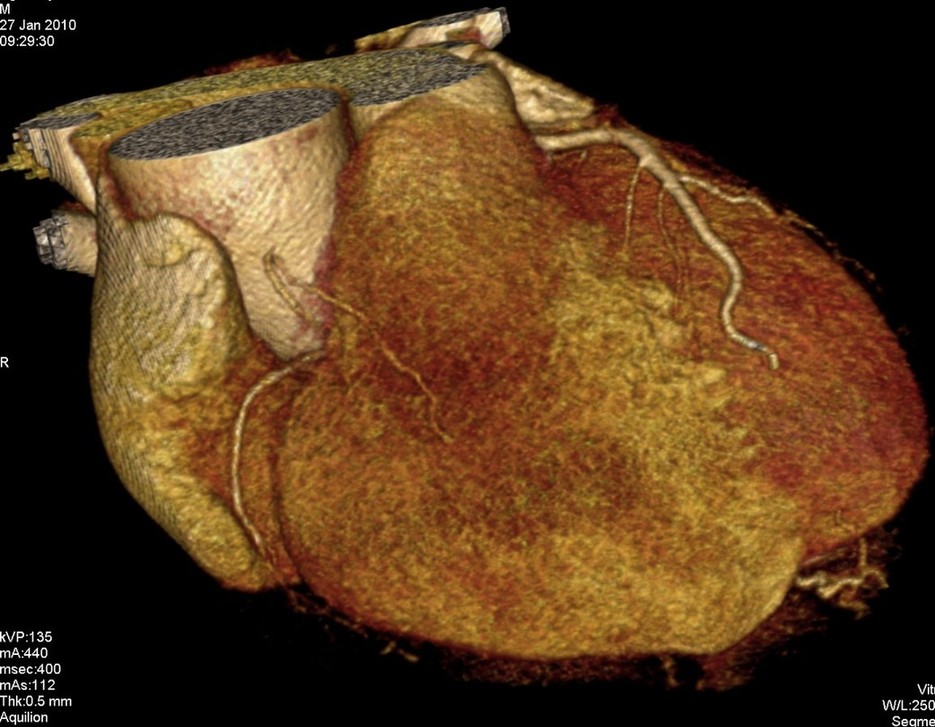

标题: CT24400:患者54岁,心前区不适进行心脏冠脉造影检查。 [打印本页]

标题: CT24400:患者54岁,心前区不适进行心脏冠脉造影检查。

患者54岁,心前区不适进行心脏冠脉造影检查。高手看看有问题没有?